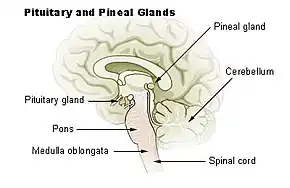

La glande pinéale ou épiphyse est une petite glande endocrine de l'épithalamus du cerveau des vertébrés. À partir du tryptophane, elle sécrète la mélatonine et joue donc, par l'intermédiaire de cette hormone, un rôle central dans la régulation des rythmes biologiques (veille/sommeil et saisonniers). Connue depuis au moins l'époque de Galien (au IIe siècle apr. J.-C.), la glande pinéale était baptisée kornarion (littéralement : pignon de pin).

Cerebellum = cervelet

Pituitary gland = hypophyse

Pons = pont de Varole

Medulla oblongata = bulbe rachidien

Spinal cord = moelle spinale.

La glande pinéale est localisée au contact du sillon cruciforme de la lame quadrijumelle constituant la région dorsale du mésencéphale, et appartient à l'épithalamus. Elle est reliée au diencéphale de chaque côté par les pédoncules antérieurs et latéraux dans l'écartement desquels, appelés triangle habénulaire, se logent les habenula.

Dans l'espèce humaine, la glande pinéale a la forme d'un pignon de pin (d'où l'adjectif pinéale) ou d'un petit cône d'environ 8 mm situé en position médiane en arrière du troisième ventricule, entre les deux thalamus, au-dessus des colliculi supérieurs, et derrière la stria medullaris.